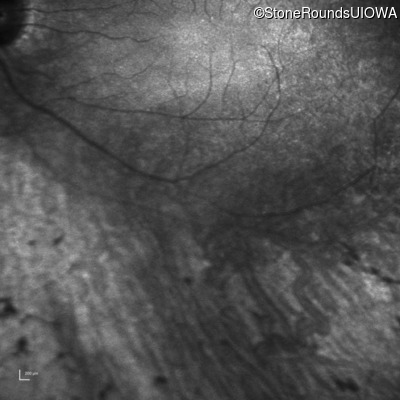

Infrared Fundus Photograph - Left - 20/80 -1

Exemplar